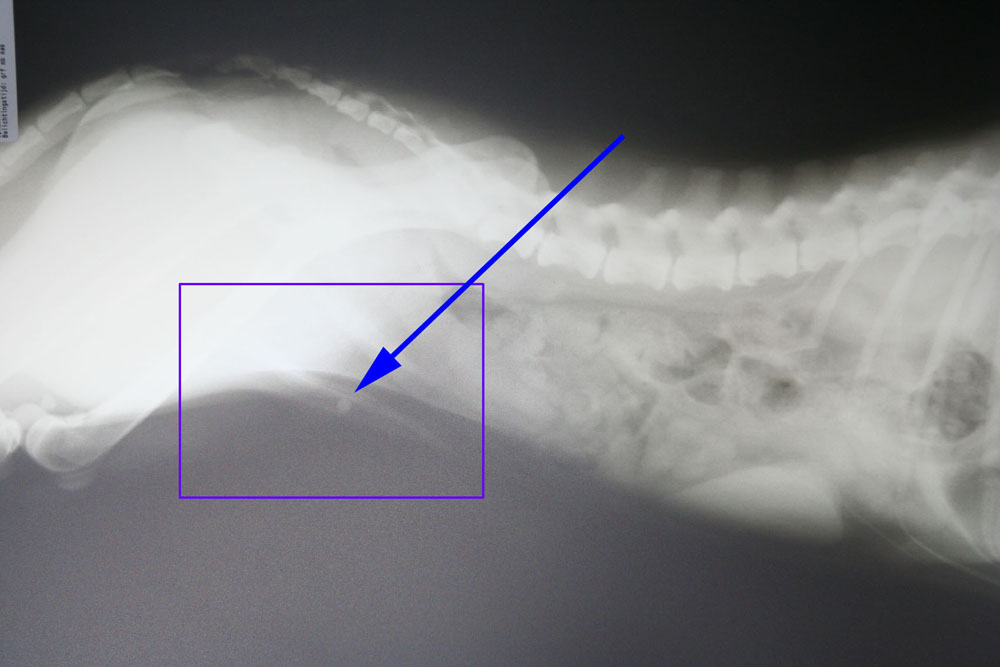

Hierna hebben we een urinekatheter ingebracht die na 4 cm vastliep op een harde structuur. Op de röntgenfoto is er bij de pijl een blaassteen te zien die vastgelopen is in het penisbotje.

Na verder onderzoek verricht te hebben kwamen we tot de conclusie dat er in de blaas zelf nog wat gruis zat en mogelijk zeer kleine steentjes.